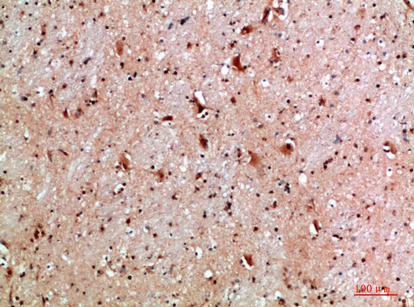

分类: 科研抗体货号: P43500别名: Epsilon Tubulin应用: IHC反应种属: Human,Mouse,Rat